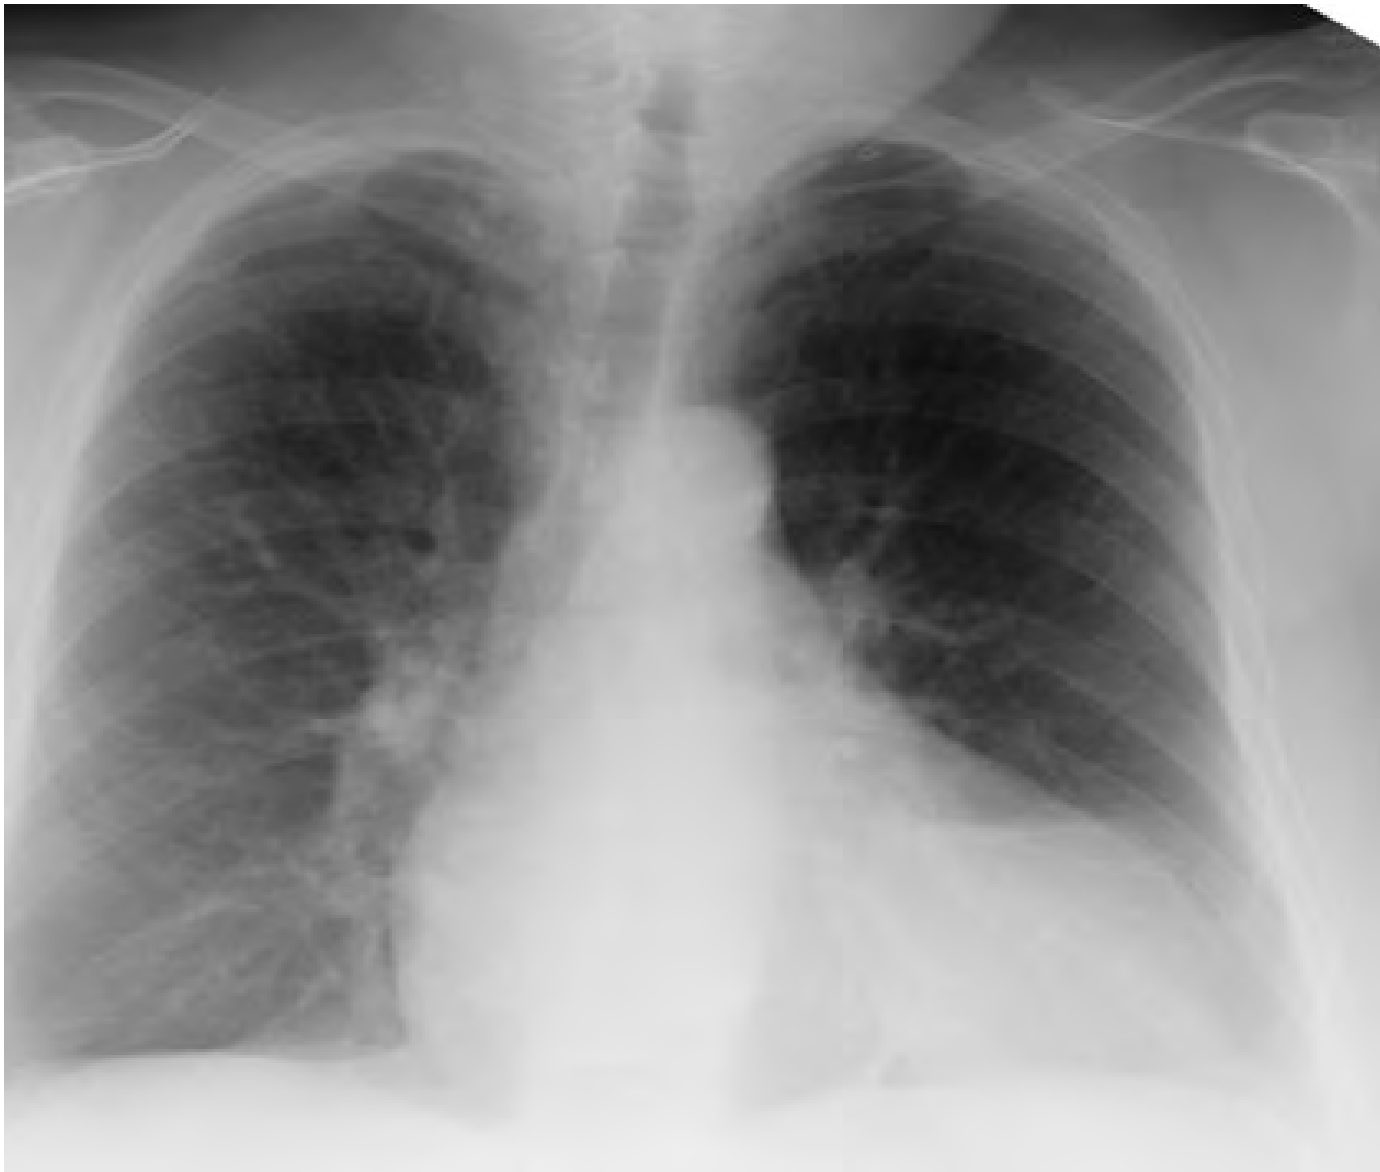

Image Chest XRay of a Patient with Cardiomegaly and Cephalization Cephalization Definition Chest X Ray Congestive heart failure (chf) is the result of insufficient output because of cardiac failure, high resistance in the. cephalization is defined as a redistribution of blood into the upper lobe vessels and can be diagnosed when the. as pulmonary venous pressure increases in heart failure the pulmonary vascular bed recruits the upper lobe. The initial phase of cardiogenic. Cephalization Definition Chest X Ray.

Chest Xray in posteroanterior projection. Cephalization of the Cephalization Definition Chest X Ray as pulmonary venous pressure increases in heart failure the pulmonary vascular bed recruits the upper lobe. Congestive heart failure (chf) is the result of insufficient output because of cardiac failure, high resistance in the. The initial phase of cardiogenic pulmonary edema is manifested as redistribution of the pulmonary veins. cephalization is defined as a redistribution of blood into. Cephalization Definition Chest X Ray.